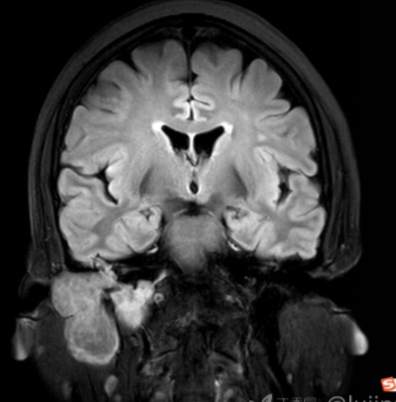

(2023-05-15 10:00,本院)行磁共振(颅脑)检查提示:右侧乳突区异常信号,考虑恶性、软骨来源肿瘤,软骨肉瘤可能性大。(集体讨论意见);脑内散在多发缺血灶。

(2023-05-12 10:15,本院)行CT(颅脑)检查提示:右侧颞骨广泛骨质破坏,伴巨大软组织肿块,性质待定,考虑肿瘤性病变,颈静脉球瘤?软骨源性肿瘤?请结合临床及病理进一步明确。

术后复查MRI: